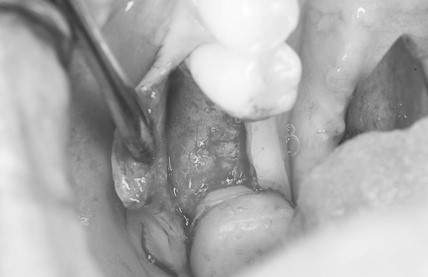

インプラント治療の症例5

レントゲン写真

- Before

- After

口腔内写真

- 途中経過

| 年齢 | 60代・女性 |

|---|---|

| 主訴 | 左下6番、7番 歯ぐきの腫れが気になり来院。 歯周病がかなり進行しており骨がほとんどない状態で動揺もあった。 |

| 治療内容 | インプラント治療 動揺がひどく歯を残すことが難しいため抜歯へ。 その後骨造成を行いインプラントを埋入。 |

| 治療費 | 合計:1,683,000円 内訳 診断料:55,000円 埋入料:165,000円×2本 チタンメッシュ:55,000円×2本 GBR:110,000円×2本 サージカルガイド:66,000円 静脈内鎮静麻酔:77,000円×2回 2次オペ:22,000円×2本 仮歯:55,000円×2本 上部構造(フルジルコニア):187,000円×2本 APF(歯肉弁根尖側移動術):110,000円×2本 (2024年1月現在) |

| 治療期間 | 16ヶ月 |

| リスク・副作用 | インプラントはご自身のセルフケアに加え、歯科医院でのメインテナンスが不十分だと、歯周病になることがある。 歯ぎしり、食いしばりが強い方はインプラントの上部構造が割れてしまうことがあるため、就寝時にマウスピースの使用が必要。 |

| 治療方針 | 歯周病がかなり進行していて骨吸収がみられるのでチタンメッシュと骨補填材を使った骨造成が必要。 先に骨造成を行い骨が再生されるのを待って埋入手術を行う。 歯ブラシがしやすくなるようにAPF ( 歯肉弁根尖側移動術 )も行う。 |

| 特記事項 | 今回は印象材ではなく光学スキャナーを使用して型どりを行った。 |

| 担当者所見 | 骨が再生するか難しいところだったが無事埋入でき問題なく結合できた。 また今回は印象材ではなく光学スキャナーを使用して印象したため患者さまの負担がかなり軽減されたと思う。 上部構造セット後しっかりとかめている。 今後も定期的にメインテナンスしていく。 |